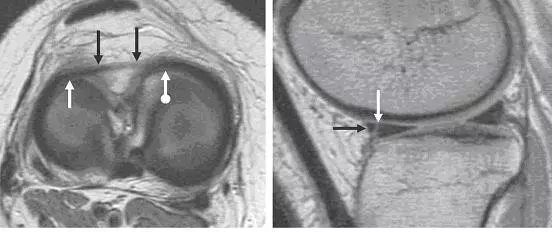

左图:外侧半月板,由于横截面面积一致,故在MRI 上可见外侧半月板前后角(纵向白色箭头)形状和大小较相似。上下腘肌半月板纤维束(黑色箭头)在外侧半月板后角处,形成裂孔,中间有腘肌腱(水平白色箭头)通过。右图:内侧半月板,可见后角(白色圆箭头),略大于前角(白色直箭头)

左图:横断面 T1 像显示半月板横韧带连接内侧半月板(白色圆箭头)和外侧半月板(白色直箭头)的前角;右图:经过半月板横韧带(黑色箭头)的矢状面,可见半月板横韧带与半月板前角之间的间隙呈现高信号(白色箭头),易误诊为半月板撕裂。